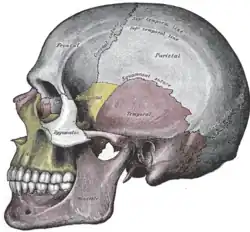

Ossos faciais

Vista lateral

Vista lateral do crânio